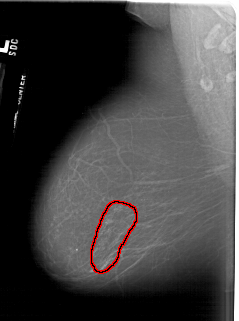

A_1617_1.LEFT_MLO

LEFT_MLO LINES 6091 PIXELS_PER_LINE 4531 BITS_PER_PIXEL 12 RESOLUTION 43.5 OVERLAY

FILE: A_1617_1.LEFT_MLO.OVERLAY

TOTAL_ABNORMALITIES 1

ABNORMALITY 1

LESION_TYPE CALCIFICATION TYPE FINE_LINEAR_BRANCHING DISTRIBUTION SEGMENTAL

ASSESSMENT 5

SUBTLETY 5

PATHOLOGY MALIGNANT

TOTAL_OUTLINES 1

BOUNDARY